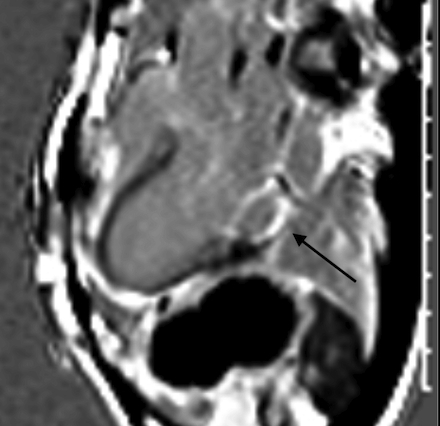

A 51-year-old African American male with history of posterior papillary muscle premature ventricular contractions (PVC), PVC induced cardiomyopathy, and family history of sudden cardiac death in his mother who presented to the emergency department due to palpitations. Electrocardiogram (ECG) showed sustained monomorphic VT at a rate of 160 bpm. This converted to normal sinus rhythm with intravenous amiodarone and metoprolol. Further work up included cardiac magnetic resonance which identified a 4 x 1.8 x 1.4 cm SMA on the basal inferior and inferolateral walls. There was near transmural late gadolinium enhancement (LGE) of the aneurysm and an associated 7 mm of MAD with posterior mitral valve prolapse (MVP). He underwent left heart catheterization which was normal. ECG showed a superior right axis with associated right bundle branch block which correlated to a basal inferolateral exit and to the location of the SMA. Ultimately the patient underwent implantation of secondary prevention implantable cardioverter-defibrillator and initiation of sotalol.